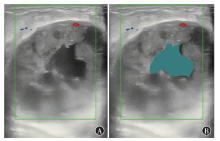

Dai Q, Tao Y, Liu D, et al. Ultrasound radiomics models based on multimodal imaging feature fusion of papillary thyroid carcinoma for predicting central lymph node metastasis[J]. Front Oncol, 2023, 13: 1261080. DOI: 10.3389/fonc.2023.1261080.

|